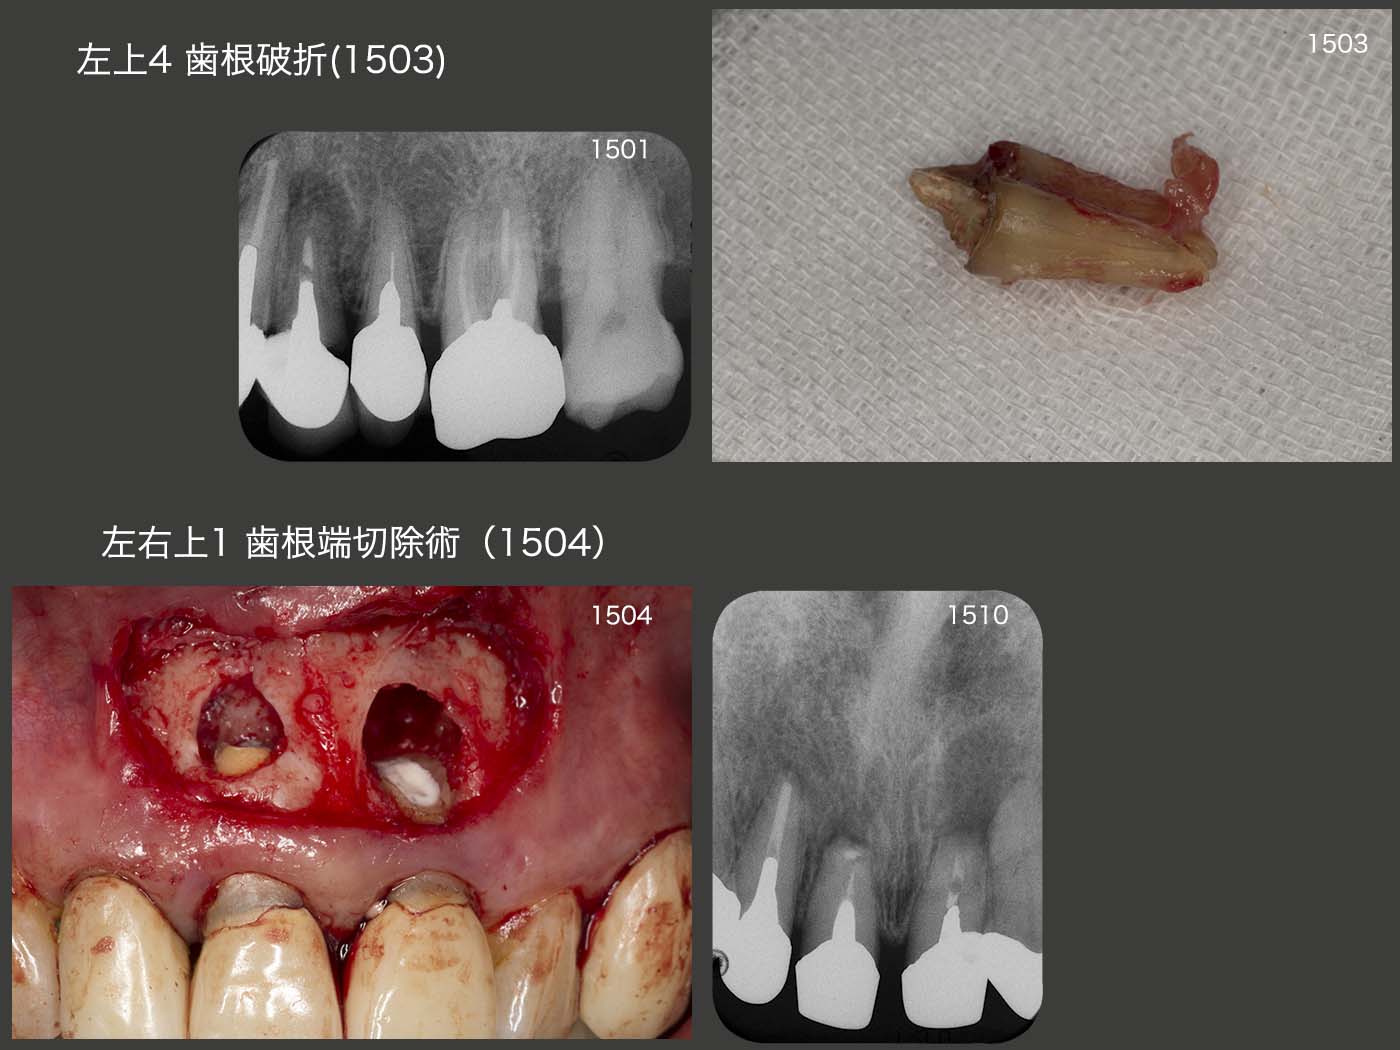

2015年1月,左上4に歯肉膿瘍が生じた.歯周ポケットが頰側に10mmあり,歯根破折を疑った.しかし,根管内から破折線がみられなかったため,念のために感染根管治療を行ってみた.2ヵ月経過をみたが,歯周ポケットが改善しなかったので抜去した.抜去歯を観察すると亀裂が確認できた.右側で咬みにくくなったため,左側で咬むようになったと同時の出来事である.

15年4月,上顎中切歯の歯根端切除術を行った.根尖は造影性のあるスーパーボンドにて封鎖したが,10月のデンタルX線写真で左の根尖にスーパーボンドの痕跡がみられない.治療の稚拙さが原因であるが,多分防湿が悪かったのであろう.